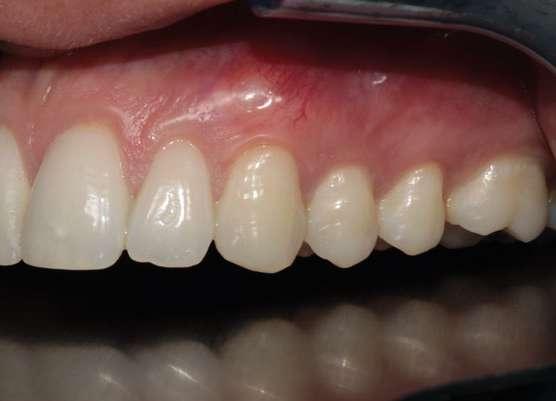

En relación con el tratamiento de este tipo de inclusiones dentarias, la literatura refiere que la extracción del canino temporal como tratamiento interceptivo es beneficiosa para la erupción espontánea del canino incluido, siempre y cuando tenga una posición y distancia favorables respecto al plano oclusal (Ahlam y cols. 2023; Almasoud 2017; Benson y cols. 2021). Debido a la etiología mencionada, es necesario conseguir espacio suficiente para favorecer la erupción del canino retenido en aquellos casos que no lo tenga, con aparatología fija multibrackets o alineadores. En otros casos, la expansión rápida del maxilar y la posterior colocación de una barra transpalatina, seguidas de la extracción del canino deciduo, son opciones de tratamiento interceptivo eficaces para pacientes de 9 a 13 años que presentan caninos palatalmente desplazados (Baccetti y cols. 2011).

Actualmente, la tomografía computarizada de haz cónico (CBCT por sus siglas en inglés: Cone Beam Computed Tomography) y la reconstrucción 3D nos permiten ver con más claridad la posición del canino y su relación con estructuras adyacentes (Alqerban y cols. 2009). En el año 2000 se desarrolló un nuevo método para evaluar, a partir del CBCT, la dificultad prevista para posicionar un canino incluido, el índice KPG. Este índice clasifica la posición del canino en función de su distancia de la norma, dando un número en una escala de 0 a 5 tanto para la

cúspide como para la punta de la raíz. La suma de las seis puntuaciones obtenidas evalúa la dificultad prevista del canino (Dalessandri y cols. 2013).

La impactación de los caninos permanentes superiores es la segunda forma más común de impactación de dientes después de los terceros molares, siendo dos veces más común en mujeres que en hombres (Becker y cols. 2015). La erupción del canino permanente suele ocurrir alrededor de los 11 años, por lo que la sospecha de su inclusión suele comenzar a los 14-15 años. La impactación palatina es más frecuente que la impactación vestibular (3 veces) y la unilateral más común que la bilateral (Chung y cols. 2011). La etiología es multifactorial y podría estar relacionada, entre otras causas, con discrepancias en el tamaño del diente y la longitud de arcada, genética, erupción tardía, deficiencia transversal del maxilar, migración dentaria, traumatismo en el maxilar o agenesia/anomalía de posición en incisivo lateral (Martínez Madero y cols. 2022; McConnell y cols. 1996).

Clínicamente, los caninos incluidos se caracterizan por la erupción retardada del canino permanente, la erupción asimétrica de ambos caninos, la ausencia de protuberancia canina en el fondo de vestíbulo o presencia de protuberancia palatina en la región canina, el retraso en la erupción o migración distal de incisivos laterales permanentes, la retención prolongada de canino temporal sin movilidad y pérdida de vitalidad o el aumento de movilidad de incisivos permanentes (Mason y cols. 2001).